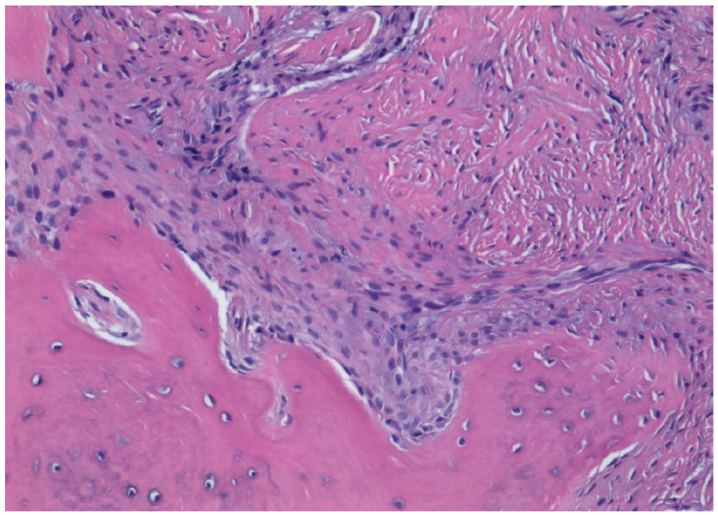

3.2. Histological Observation